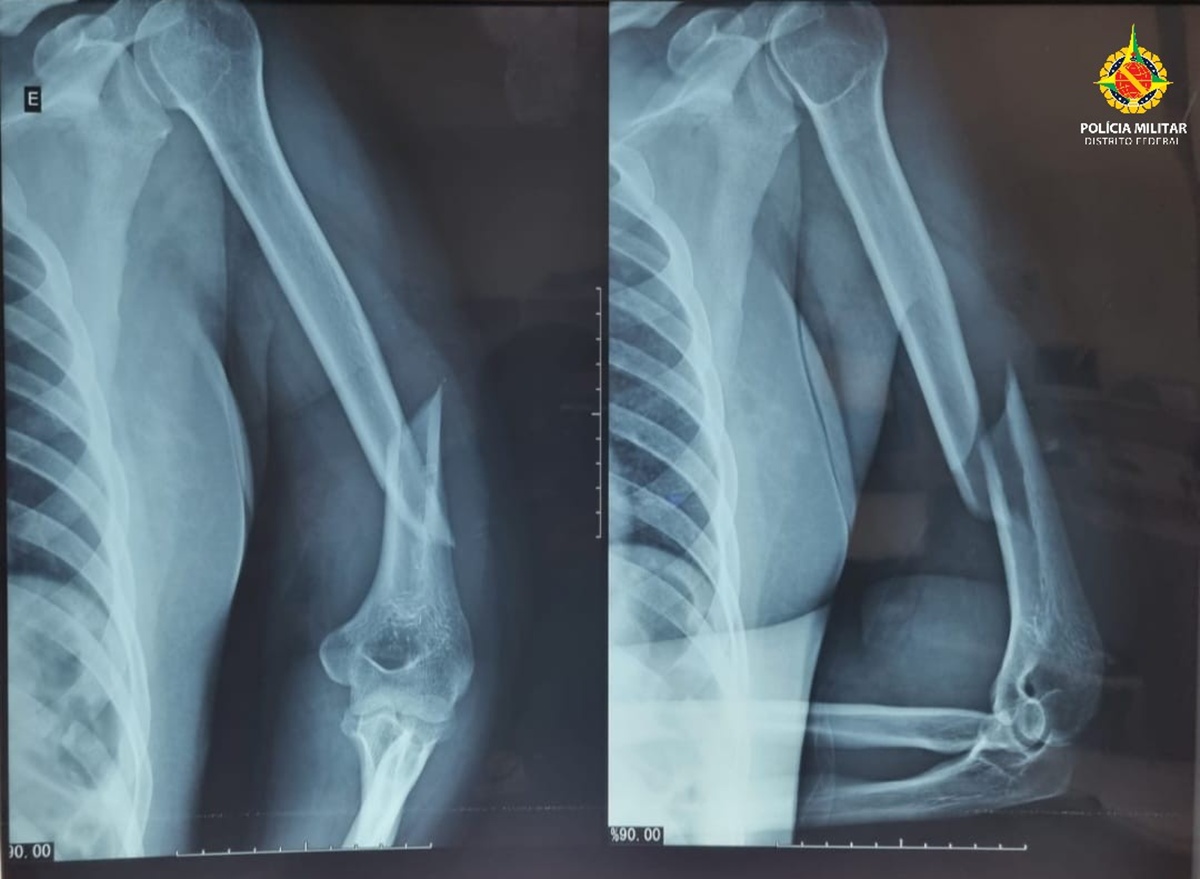

A Polícia Militar do DF (PMDF) recebeu um chamado de violência doméstica e, ao chegar ao local, encontrou a vítima, de 41 anos, com hematomas no rosto, inchaço ao redor dos olhos, sangramentos nos ouvidos, fraturas e luxações. Uma equipe médica do Samu avaliou que ela apresentava sinais de traumatismo cranioencefálico.

De acordo com a mulher, os abusos começaram à meia-noite e se estenderam até a manhã. Ela contou que uma vizinha ouviu seus gritos de socorro e acionou a PMDF. A vítima foi levada ao Hospital Regional de Taguatinga, onde permanece internada e aguardando cirurgia.